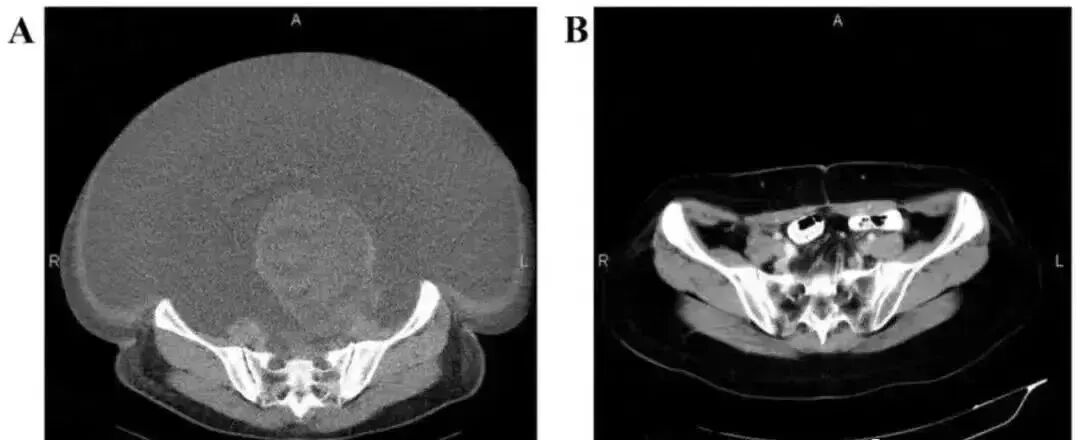

03 卵巢癌:腹水消失,肿块体积减小

国内一名60岁的卵巢癌晚期患者,在接受了体外扩增,高度活化的同种异体NK细胞的治疗后,CA125水平从11,270降至580,所有腹水都消失了。此外,CT扫描的肿块体积减小,并且没有出现副作用。

有一项研究NK细胞治疗卵巢癌的临床试验,收集包括14名卵巢癌患者,他们先接受了化疗的预处理,然后接受异体NK细胞和IL-2的静脉内灌注。尽管没有观察到NK细胞在体内的持续扩增,但治疗后三个月的CT扫描显示,4名患者实现了部分缓解,8名患者病情稳定。